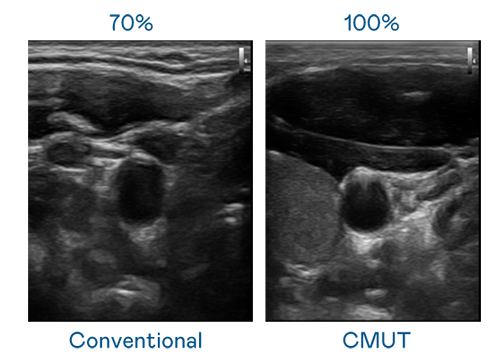

CMUT 技术是一种用电容式微机电元件来产生超音波讯号的技术。与传统 PZT 压电式技术相比,CMUT 频宽增加 30%,更宽频的超音波讯号让影像解析度大幅提升,是实现高影像品质医疗超音波扫描、促进精准医疗发展的关键技术。

超音波影像的解析度高低,首先取决于探头能发出的讯号频宽。德扑之星 CMUT 可提供高清晰的超音波讯号,提供高频宽、高灵敏度、影像纹理细节更高的超音波影像,协助医护人员缩短影像判读时间及利用精准的医疗影像进行诊断。